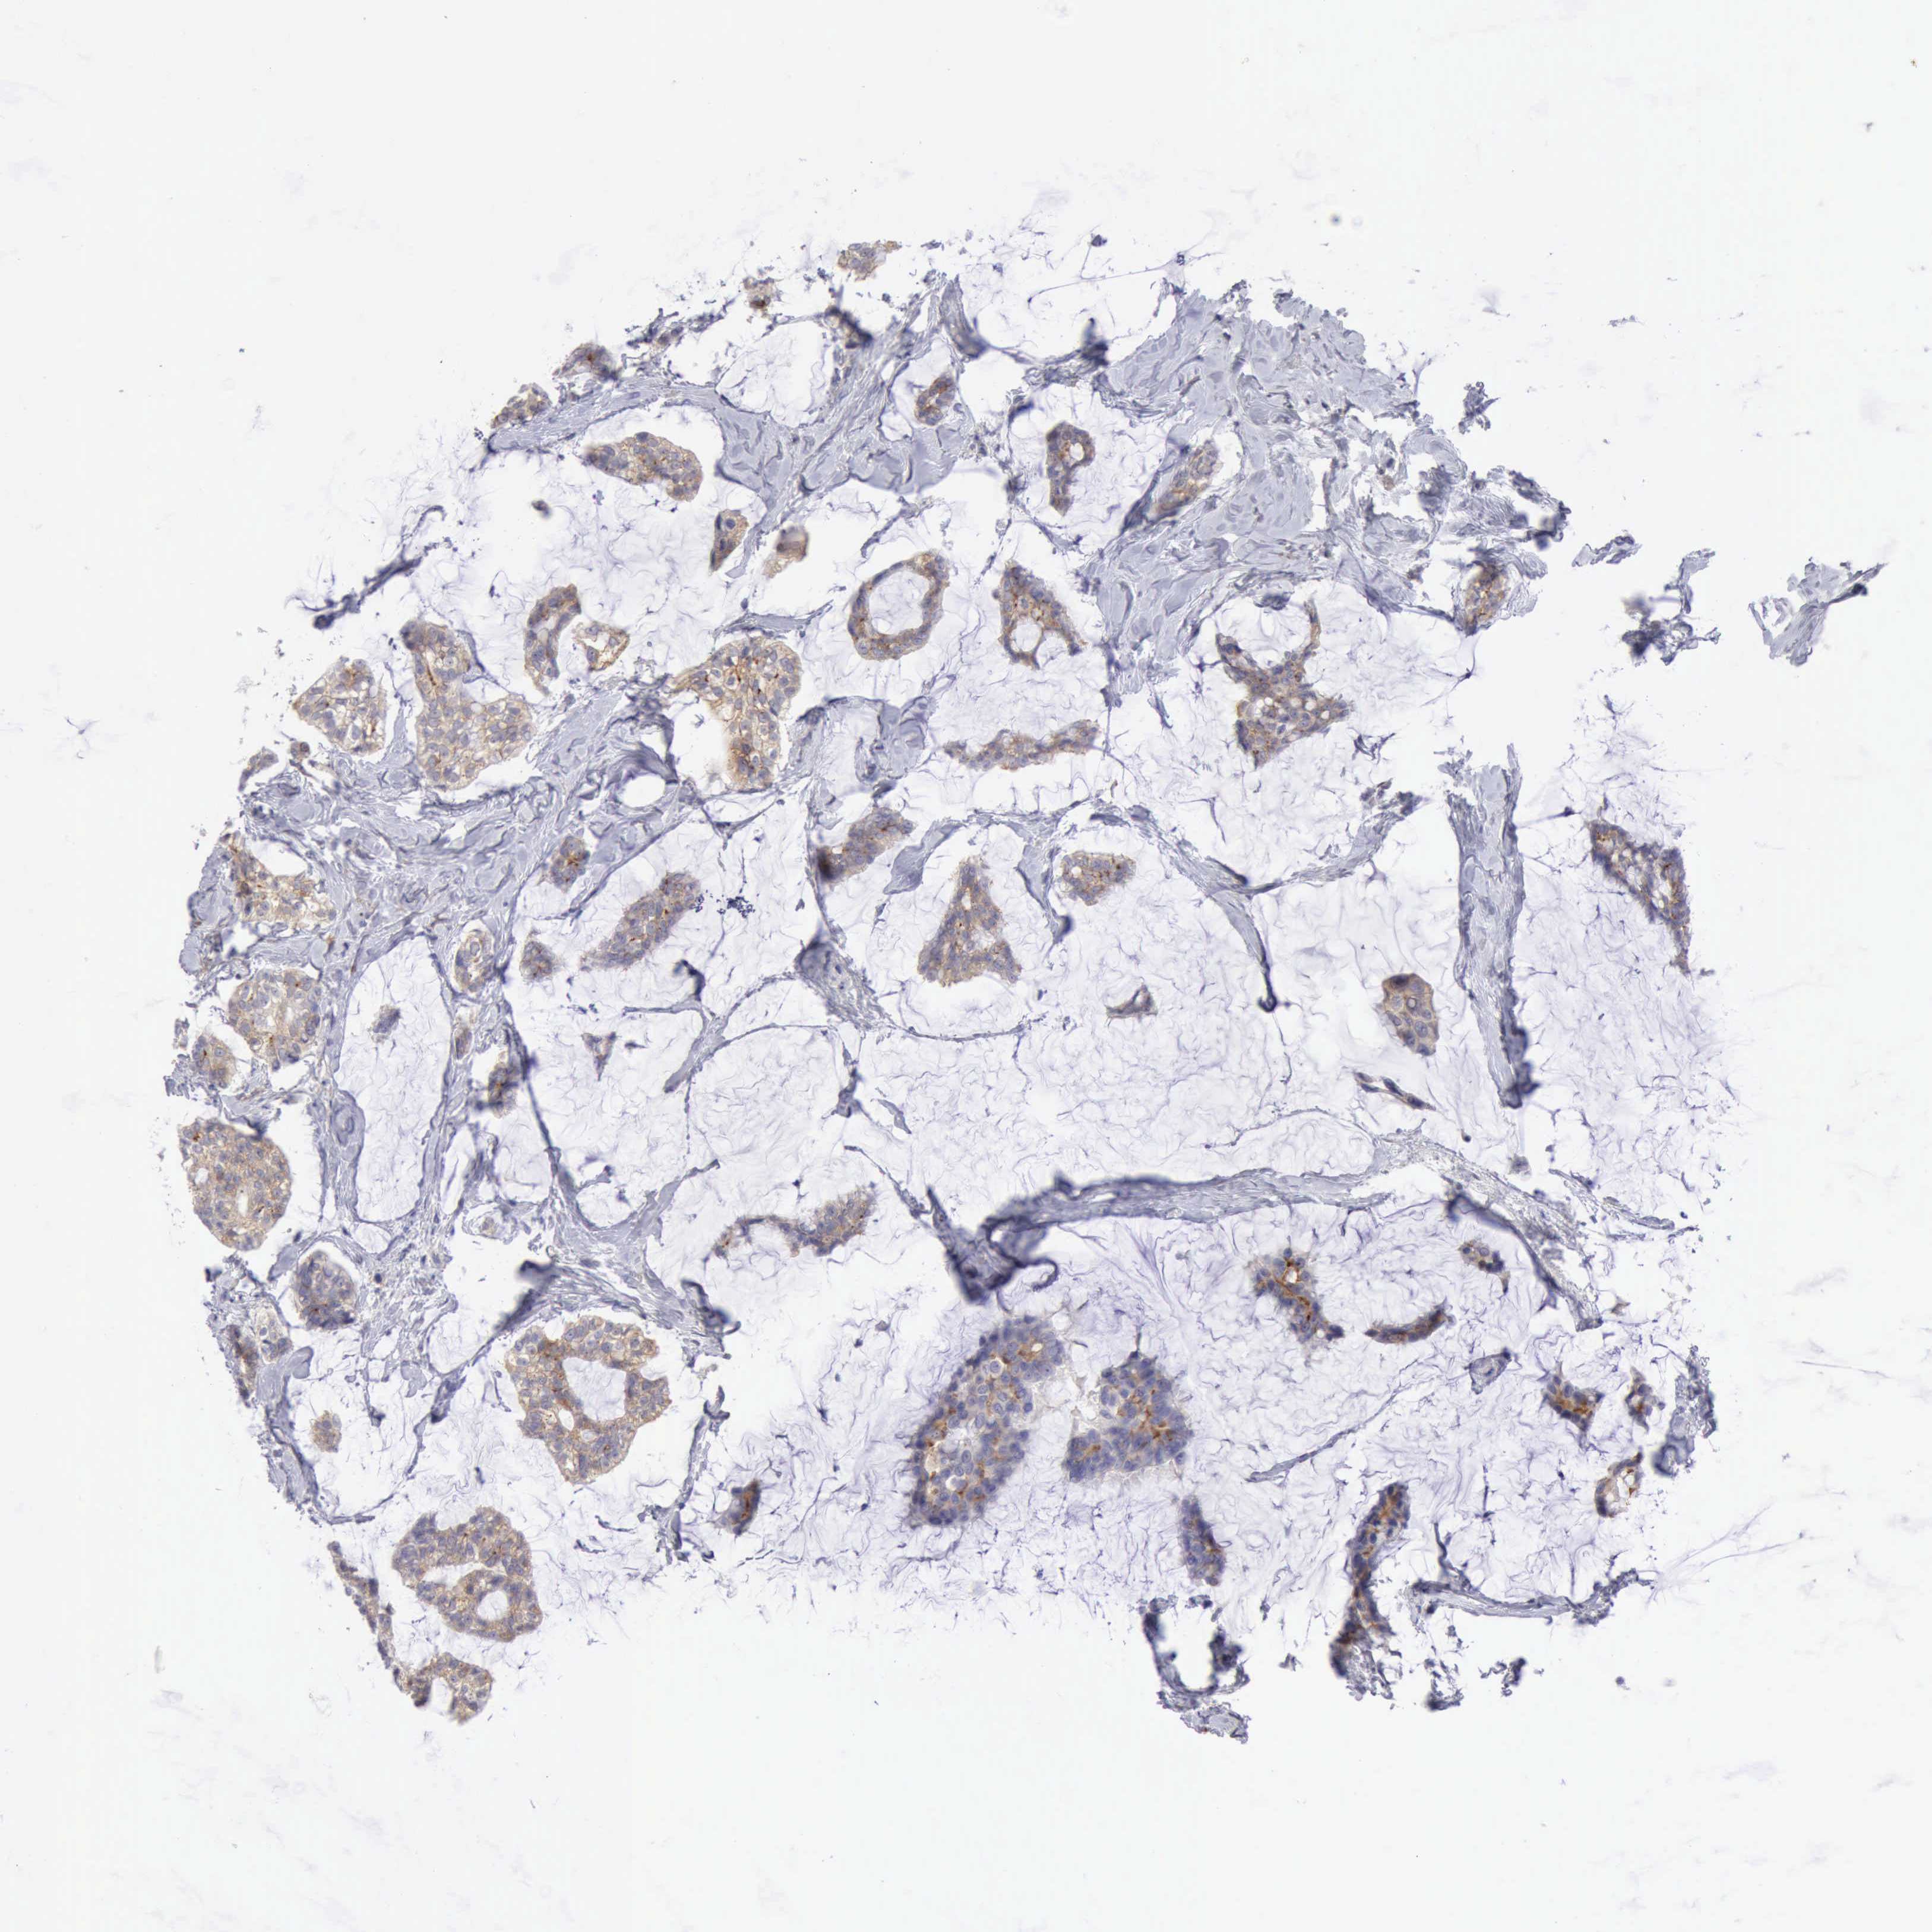

Breast cancer

Human cancer